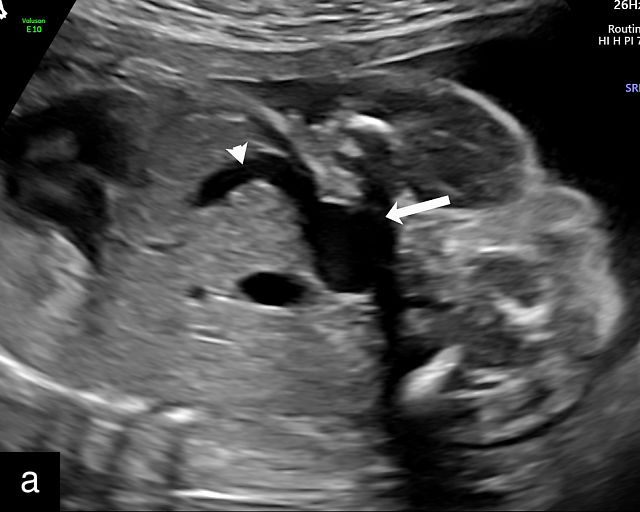

There are three types of vasa previa.30,262 In Type 1, the cord inserts into the membranes rather than the placenta. Unprotected vessels then traverse the membranes over the cervix to insert into the placenta (Figure 21a; Video 12). In Type 2, unprotected vessels running through the membranes over the cervix connect the main placental lobe with an accessory lobe (Figure 21b).263 In Type 3, there is generally a normal placental cord insertion, and unprotected vessels exit one placental edge, run through the membranes over the cervix and then boomerang to insert into the placental edge at another site (Figure 21c).25,28,29,264 Regardless of the type, all these expose the fetus to the same risks.

21